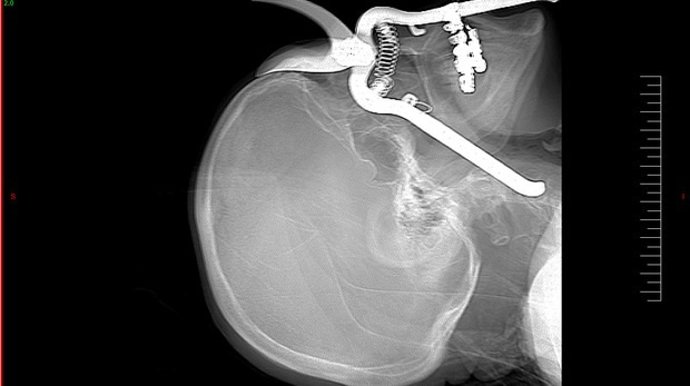

Discovery Max estrena este miércoles, 23 de enero, la serie 'Urgencias Punzantes', donde todo tipo objetos terminan clavados en el cuerpo de las víctimas. Todos estos errores médicos y trágicos accidentes podrán verse a partir de las 00.25 horas.

En esta serie inédita en televisión, los espectadores serán testigos de garrafales errores médicos y descuidos en el quirófano con un denominador común: el cuerpo humano se convierte en el anfitrión de los más extraños objetos que deciden insertarse en él de la manera más terrorífica.

Integrada por seis entregas de una hora de duración cada una, 'Urgencias Punzantes' narra los sucesos más extraños que acabaron con los protagonistas de la serie atravesados por accidente y con una situación médica de riesgo extremo, con complicada solución.

Situaciones bizarras y asombrosas que enseñan no sólo a extremar las precauciones, sino a mantener el control cuando los objetos más extraños (verjas, piezas de aviones, anillos de compromiso, cubertería o cemento) se cruzan en el camino.

A través del testimonio de las víctimas, de declaraciones de testigos, recreación del suceso y el uso de impactantes imágenes generadas por ordenador, la serie ofrecerá las historias más inexplicables, inesperadas y sorprendentes.

En el primer episodio, se muestra el caso de una niña escocesa que nunca imaginó que un paseo por la calle acabase con una valla metálica clavada en su propia cara. Otro de los casos más llamativos es el de un jardinero que, tras un descuido con la máquina corta césped, terminó con las tijeras de podar en su cráneo.